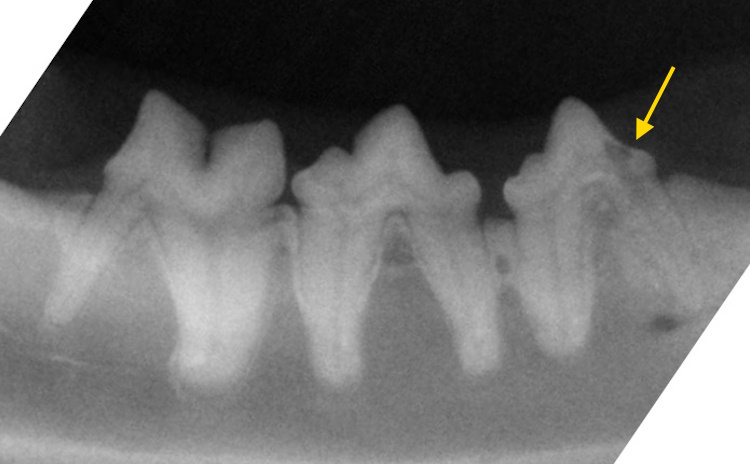

Lower third premolar tooth affected by tooth resorption.

Another cat with lower third premolar tooth affected by tooth resorption.

Resorptive lesion can be seen on the crown and neck of the tooth. This is a Type 1 lesion (the root appears normal, and periodontal ligament space is still observable).

This tooth is severely affected by resorptions. This is a Type 2lesion (exhibiting root replacement by bone with no clearly observable periodontal ligament space).